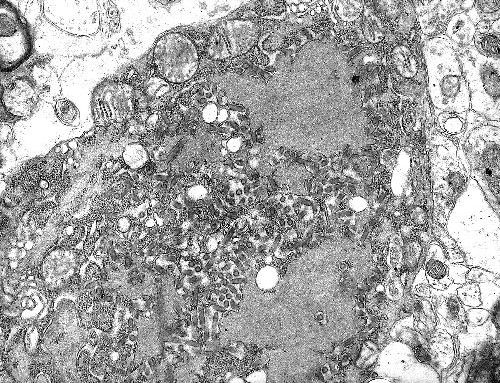

虽然它长得很像“如意”,但是碰到了一点都不如意。埃博拉病毒的生物安全等级(越大越危险)达到了4级,死亡率在50%—90%之间。是传染性和致死率极高的病毒之一了。